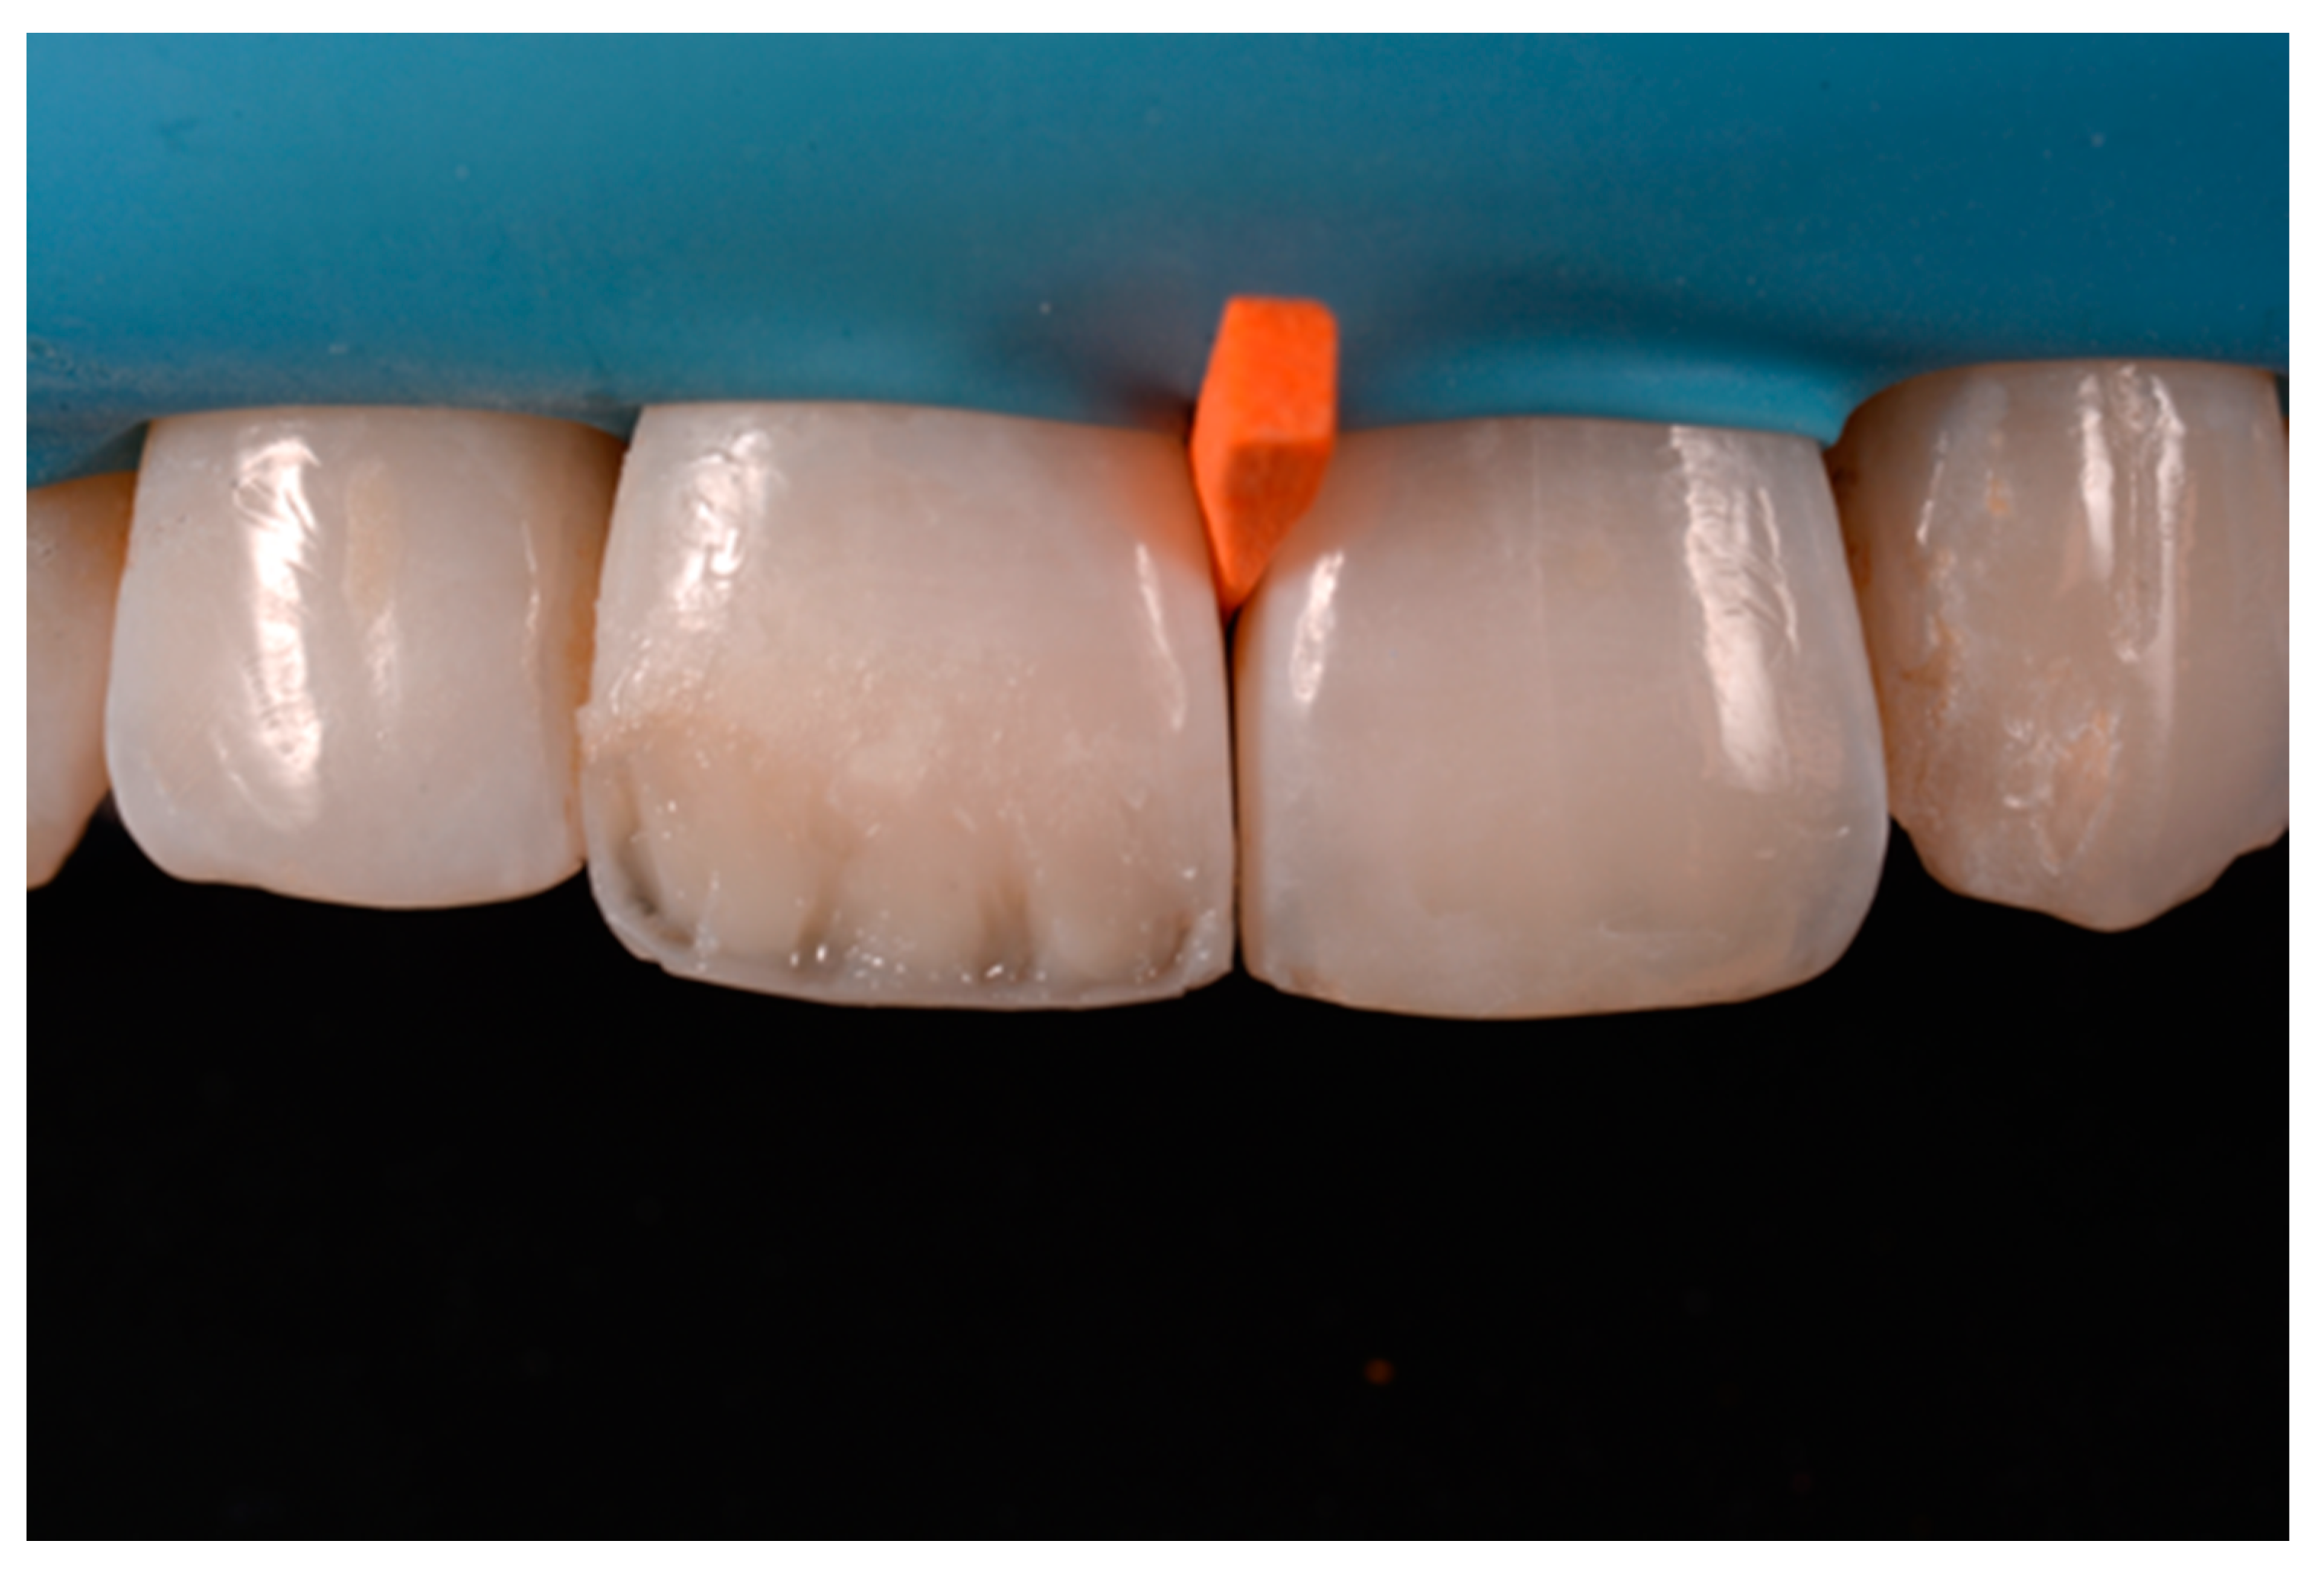

Before isolation with rubber dam, shade was selected using the button-try technique [14] applying composite samples on the teeth and light-curing them without performing previous adhesive procedures. The silicon index was checked in situ (Figure 4) and interferences were removed with scalpels. A two-step self-etch adhesive system (Clearfil SE Protect, Kuraray Noritake Dental, Tokyo, Japan) was applied following manufacturer’s instructions after selective enamel etching with a 38% phosphoric acid gel (Ultra-Etch, Ultradent Product, Inc., South Jordan, UT, USA). Light curing was applied with a visible light-curing unit with an intensity of 1000 mW/cm2 (Valo, Ultradent Products, South Jordan, UT, USA) for 20 s. A thin layer of composite enamel (Clearfil Majesty ES-2, A1E, Kuraray Noritake Dental, Tokyo, Japan) was applied on the silicone index in order to reproduce the palatal wall. The silicone index was then repositioned in the mouth and the palatal composite was adapted to the palatal margin of the preparation and light cured. Another increment was then applied to reproduce the incisal margin. The silicone index was then removed (Figure 5). In order to complete the frame, sectional matrices were applied vertically (Figure 6) and stabilized with wedges and interproximal drops of flowable cured to maintain the desired matrix position (Figure 6). Interproximal walls were then restored using the abovementioned composite enamel.

Figure 4.

Silicone index try-in after rubber dam isolation. Reprinted from Restauri diretti nei settori anteriori, G. Paolone, S. Scolavino, © 2021, with permission from Quintessence Publishing Italy.